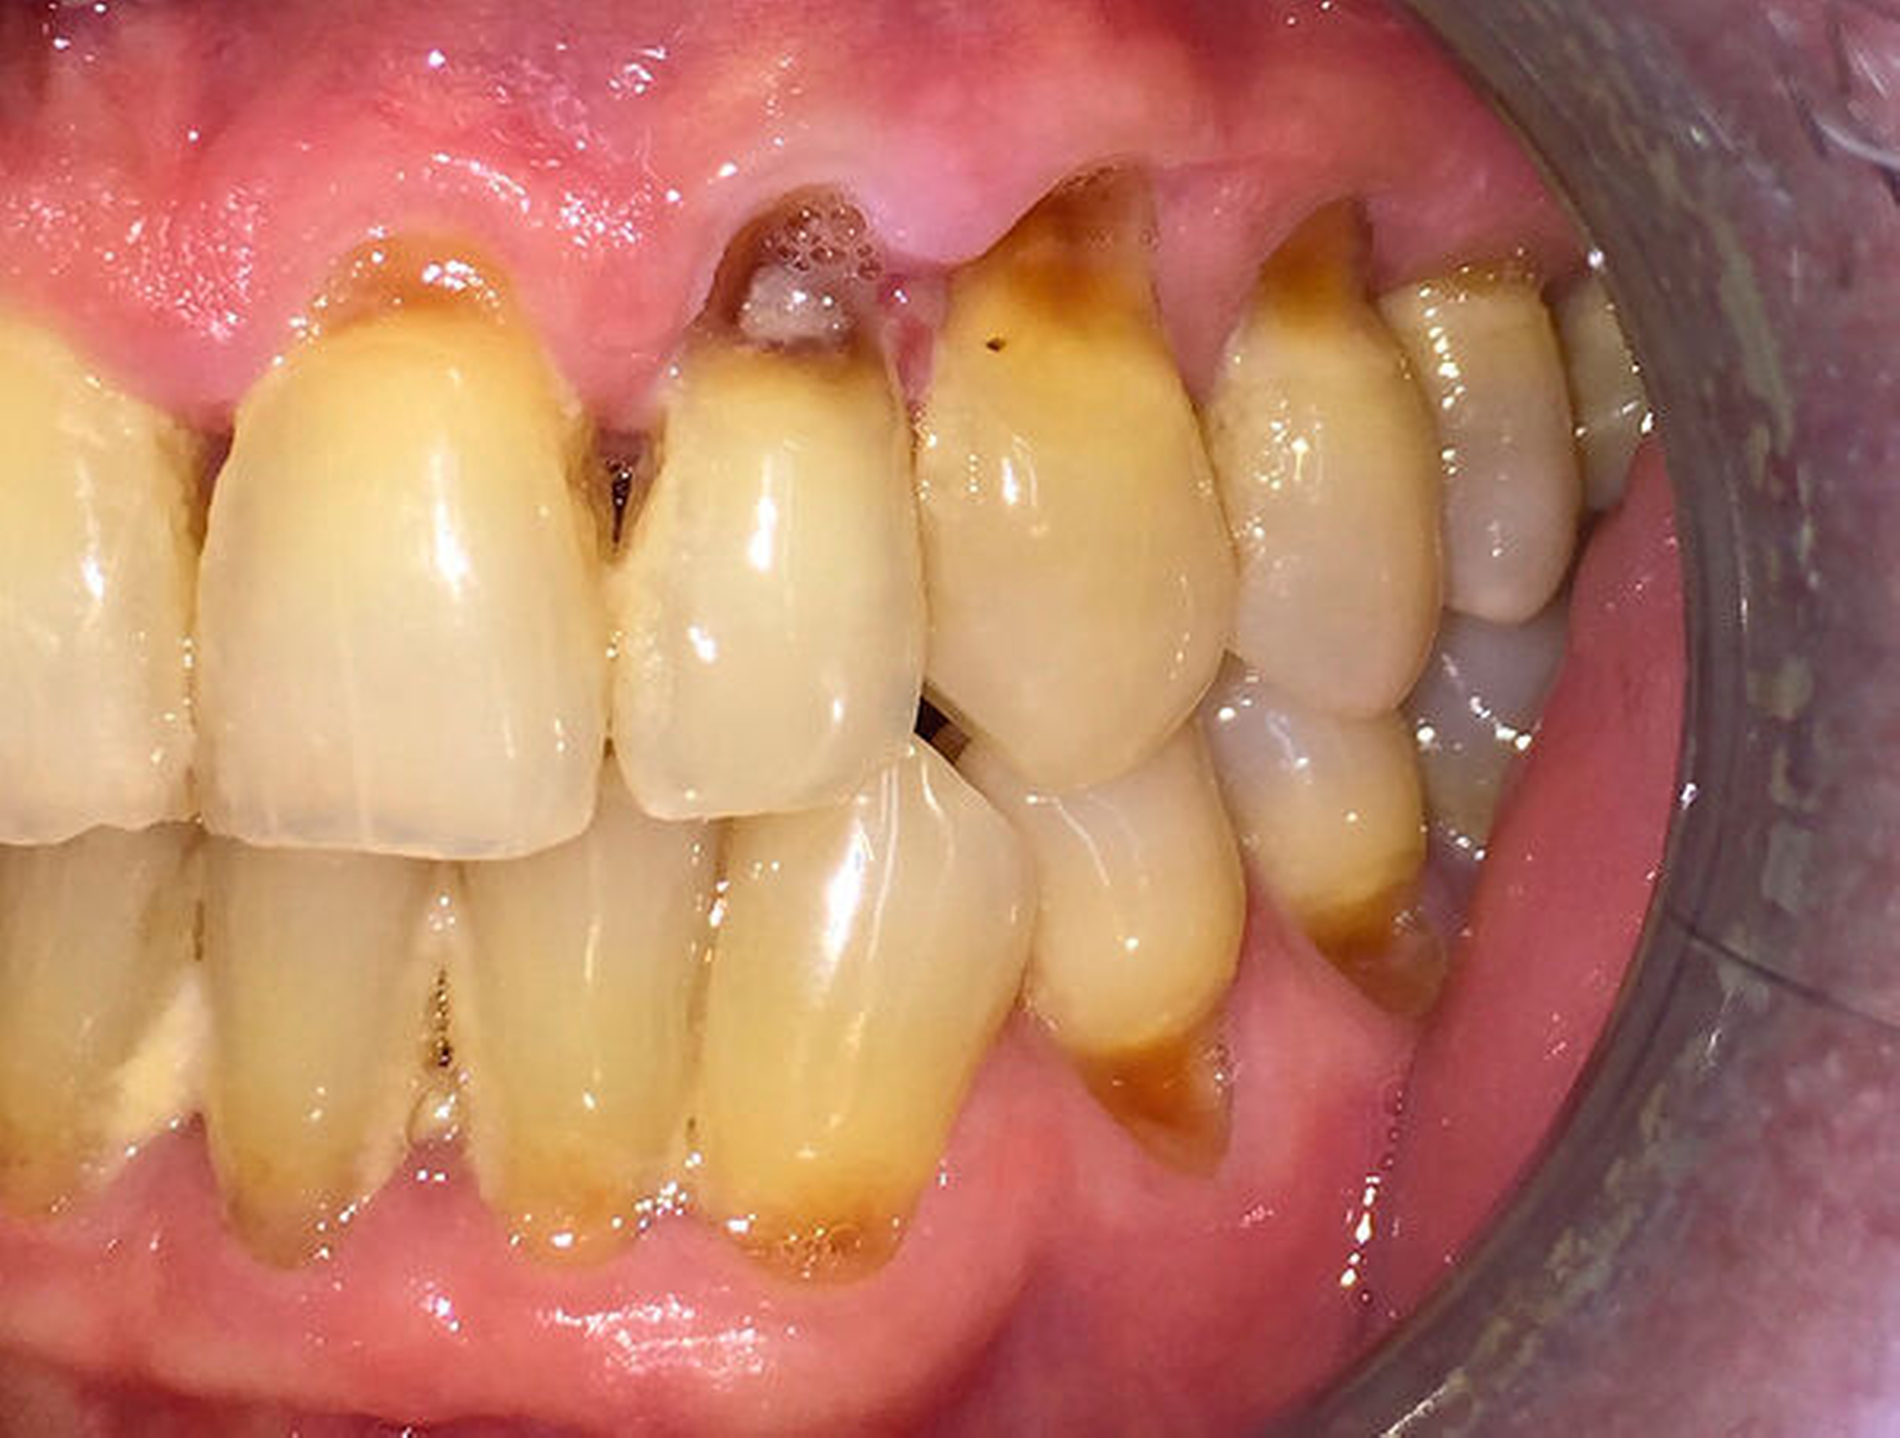

Sekundär entwickeln sich oft bakterielle, virale und mykotische Schleimhautinfektionen. Man beobachtet des Weiteren eine progrediente Zunahme kariöser Läsionen an Glattflächen, Füllungs- und Kronenrändern sowie im Bereich von Wurzeloberflächen [Jaschinski et al., 2009] (Abbildung 2a).

Beide Formen oraler Veränderungen – die mehr oder weniger stark ausgeprägten Verminderungen des Speichelflusses und die gingivalen Wucherungen – bereiten dem Zahnarzt häufig große Probleme. Als Folge der fehlenden protektiven Wirkung des Speichels können sich kariöse Läsionen – besonders im Bereich der Zahnhälse – 15-mal schneller entwickeln [Jaschinski et al., 2009]. Weiterhin können in fortgeschrittenen Fällen gingivale Wucherungen die Durchführung der Mundhygiene und die Therapie von kariösen Defekten in unmittelbarer Nähe der Gingiva erschweren. Trotz der bestehenden Schwierigkeiten sollte die vom Hausarzt, Kardiologen oder Neurologen verordnete Medikation auf keinen Fall eigenmächtig verändert oder gar abgesetzt werden. Stattdessen empfiehlt sich bei beiden Patientengruppen eine Intensivierung der Plaquekontrolle durch eine individuell abgestimmte Instruktion zur Durchführung der Mundhygiene (MHD) und in kurzen Zeitabständen durchgeführte professionelle Zahnreinigungen (Abbildung 2).